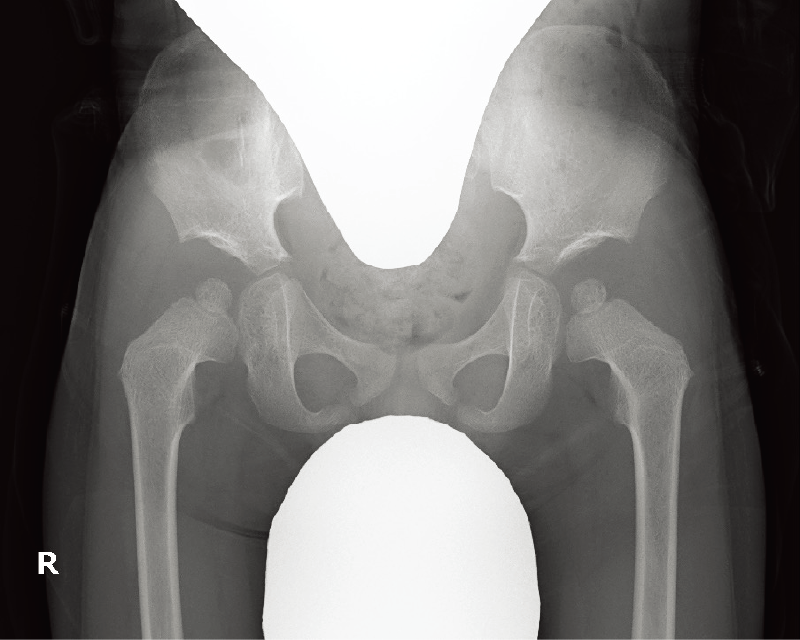

罹患症例の10~20%は両側性。両側性に発症する場合、通常は左右非対称で、異なる病期に発見される(A)。

特徴的な画像所見:初期には関節腔の拡大、大腿骨頭骨端部の骨硬化(B)、前外側の軟骨下骨折線(Crescent sign)を認める。後期は大腿骨頭の扁平化、分節化(A)などがみられる。

A. 両股関節正面像(年齢・性別不明):右は初期、左は進行期のペルテス病。

B. 両股関節正面像(年齢・性別不明):ペルテス病同時期発症例。